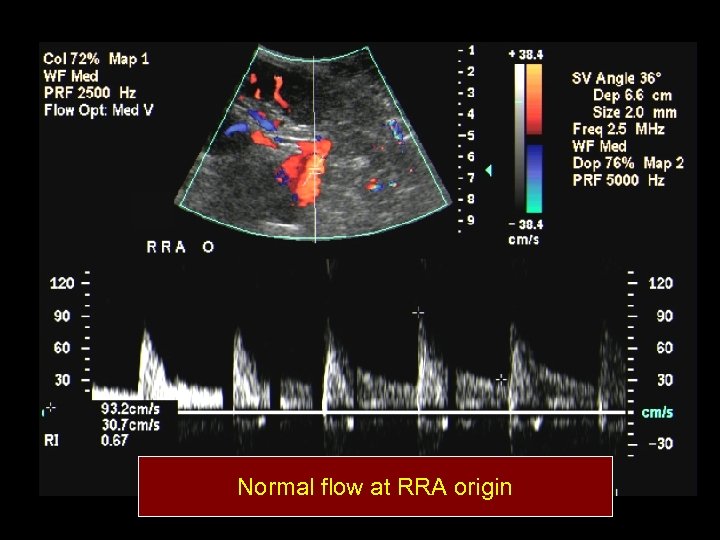

Normal flow at RRA origin